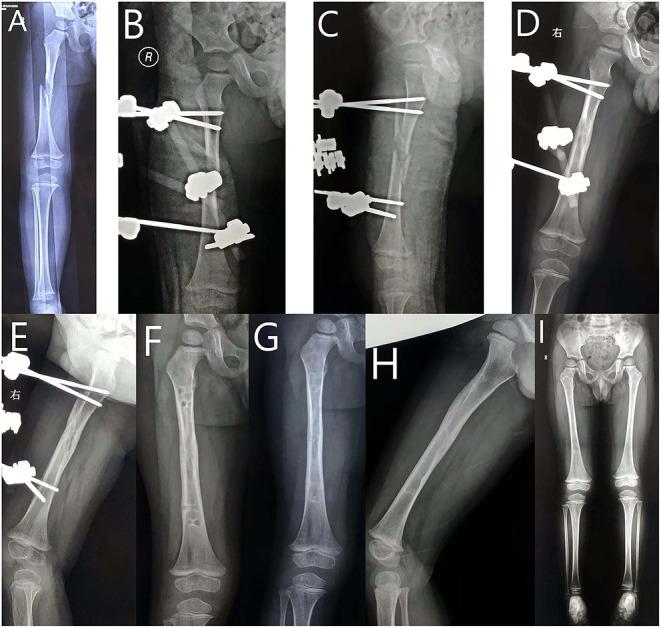

Locking plate (LP) is a good choice in the treatment of length-unstable femoral shaft fracture in children. Monolateral external fixator (EF) has been reported for this condition for decades. This study aims to compare the clinical outcomes of school-aged children with length-unstable femoral shaft fracture treated with LP . EF.

Patients aged 5-11 years old with length-unstable femoral shaft fractures treated at our institute from January 2014 to January 2018 were retrospectively reviewed and categorized into LP and EF groups. The preoperative data, including baseline information of the patients, radiographic parameters, and types of surgical procedure, were collected from the hospital database, and postoperative data, including complications, were collected during the follow-up visits.

Overall, 36 patients (average, 8.2 ± 2.1 years; male, 20; female, 16) in the LP group and 35 patients (average, 8.3 ± 2.3 years; male 20, female 15) in the EF group were included. There was significantly less operative time for EF (45.4 ± 7.8 min) compared with LP (67.8 ± 11.3 min) ( < 0.001). As for the frequency of fluoroscopy, there was a significant difference between the EF (13.9 ± 2.4) and LP (16.5 ± 3.2) groups ( < 0.001). The rate of major complications was not significantly different between these two groups. There was a significant difference between the EF group (11.2 ± 5.8 mm) and the LP group (7.5 ± 1.6 mm) group concerning limb length discrepancy ( < 0.001).

Both LP and EF produce satisfactory outcomes in school-aged children with length unstable femoral shaft fractures. External fixation remains a viable choice without the necessity of secondary surgery for hardware removal.